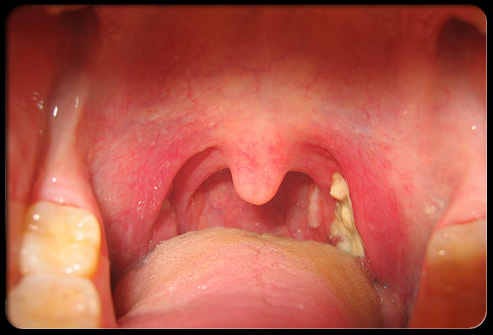

Holes In Tonsils Causes Sore Throat And More

Holes In Tonsils Causes Symptoms And Treatment

Tonsillitis

Tonsillitis Wikipedia

Tonsillitis Healthdirect